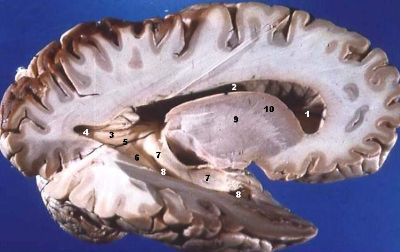

통신을 위한 고속도로 역할을 하는 백질과 기능을 담당하는 회질이 나눠져 있다는 거예요. 인류의 뇌의 성공은 필요한 모듈을 잘 만들었다는 것, 그리고 그들을 잘 연결한 점입니다.

스크린샷 2025-01-15 094318.png 안쪽은 흰색 백질 / 바깥쪽은 회색 화질입니다. 하얀색 수초로 둘러싸여 있어서 그렇습니다. 마치 윤활유처럼요.